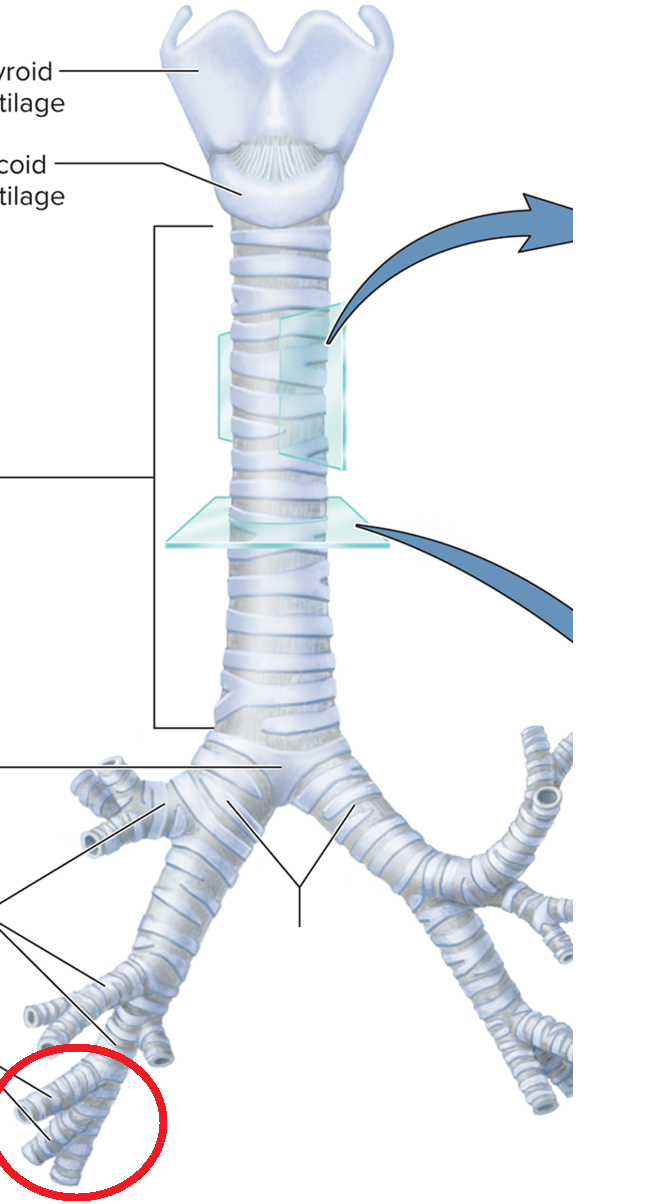

Trachea and Bronchial Tree

Carina T

Tracheal bifurcation T

Main bronchi BT

Lobar bronchi BT

Segmental bronchi BT

Bronchiole BT

Terminal bronchiole BT